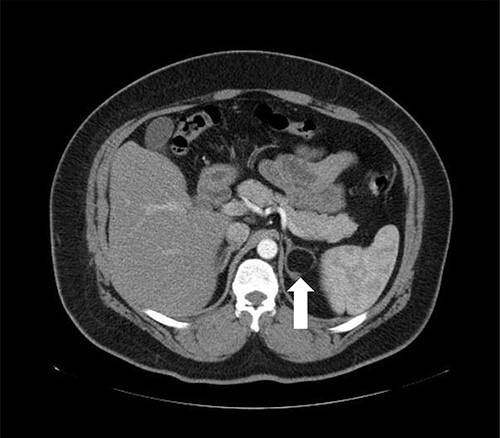

A 55-year-old male, with a BMI of 40, was referred to our surgical clinic at a governmental/academic hospital after being investigated at endocrinology department. His medical history was significant for insulin-dependent DM, uncontrolled HTN on four medications, chronic kidney disease and ischemic heart disease with multiple coronary stents on antiplatelets. A biochemical workup showed an elevated serum aldosterone of 100 ng/dl, elevated serum renin of 109 uIU/ml and elevated urinary ARR of >7000 mg/g. Serum potassium and sodium levels were within normal limits. A CECT of the abdomen and pelvis confirmed an isodense right adrenal focal lesion measuring 1.7 × 1.6 cm in pre-contrast phase, with enhancement on contrast phase followed by rapid washout, concluding a diagnosis of Conn’s syndrome (Fig. 2). Peri-operative optimization of blood pressure/cardiac status and management of anticoagulation were done through cardiac consultation. Due to his cardiac status, the patient was labeled as high risk for peri-operative cardiac events. A specialized cardiac anesthetist was consulted to perform the anesthesia.

Axial CT of the abdomen showing the right adrenal mass in Patient 2 (white arrow).